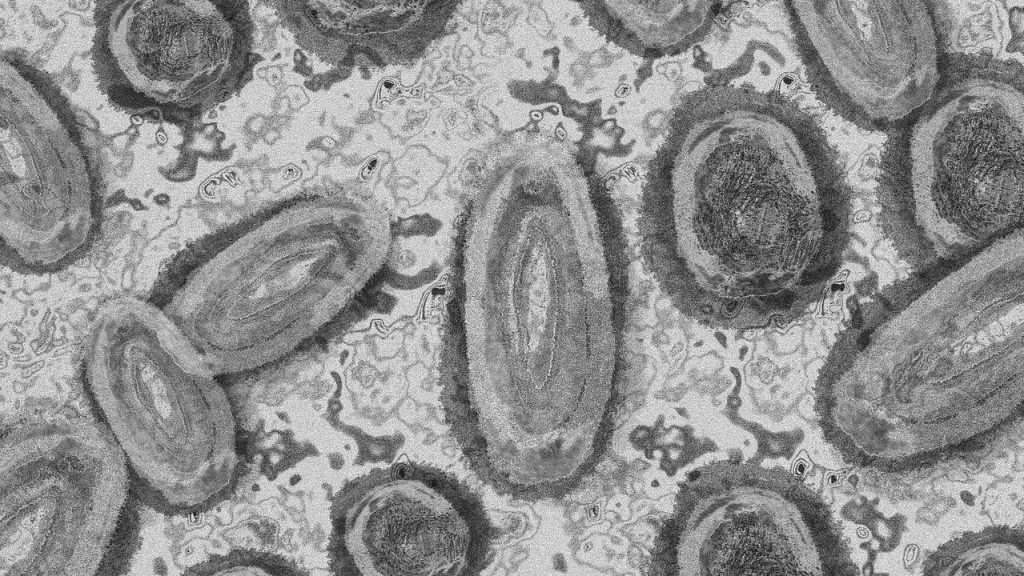

Reportan primeras muertes por viruela símica fuera de África

Este viernes se confirmaron las primeras dos muertes por viruela del mono fuera del continente africano. La primera persona fue reportada en Brasil, mientras que la segunda se registró en España, el país con más casos de esta enfermedad hasta ahora.

La Organización Mundial de la Salud (OMS) únicamente había detectado 5 muertes por viruela símica, y todas habían sido en África. A día de hoy, se tienen contabilizados más de 18 mil contagios en 78 países de todo el mundo, siendo Europa el continente más golpeado, con el 70% de los casos. América mantiene el 25% de los contagios, mientras que África, el 5% restante.